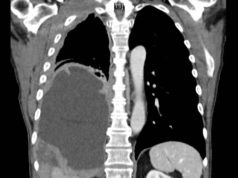

Should You Get Screened for Lung Cancer in Florida?